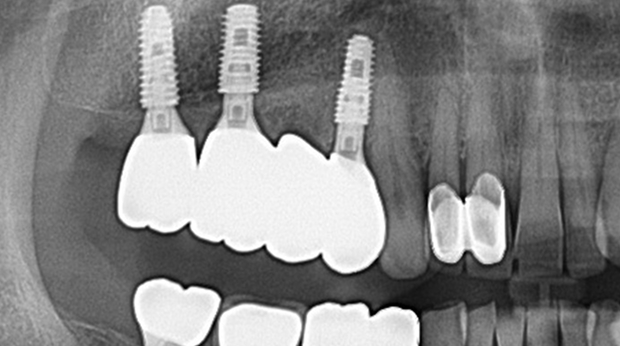

의식하진정법(수면마취)/임플란트

고난도 수술 진료

임플란트와 사랑니 발치는 외과적 시술로 잇몸을 절개하는 외과적 시술은

짧으면 짧을 수록 시술 후 붓기와 통증이 최소화됩니다.

치과의사 경력 14년차 구강외과 전문의가 빠르고 안전하게, 아프지 않게 수술해 드립니다.

치과경력 14년차 구강외과 전문의

연세대학교 치과대학 구강외과 임상 조교수